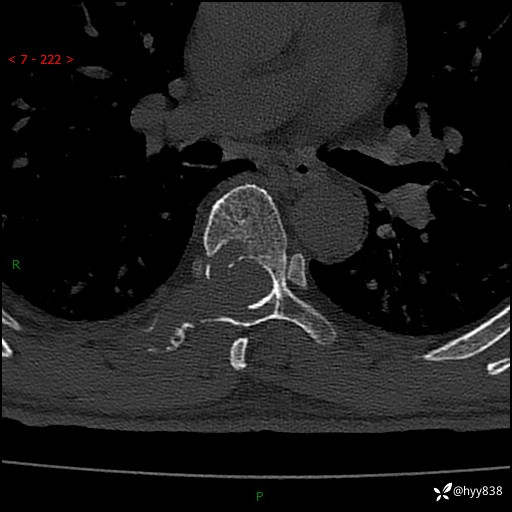

胸椎CT平扫(骨窗+软组织窗)